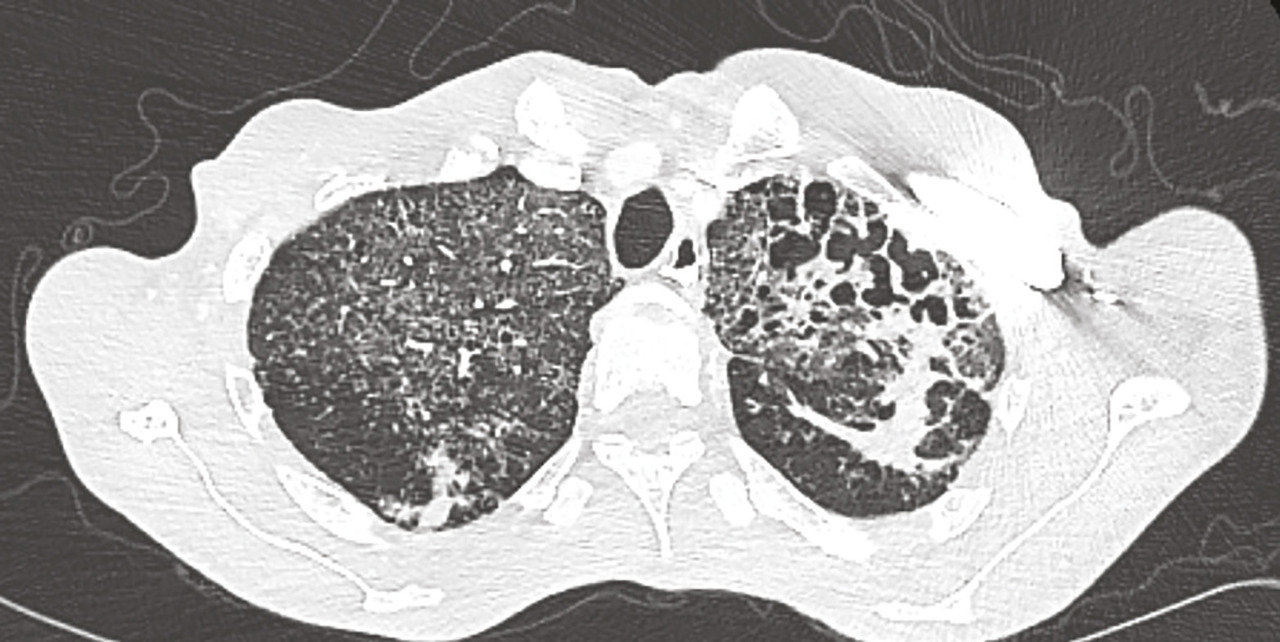

Cet homme était hospitalisé pour une fièvre avec toux et expectorations sans hémoptysie. On notait à l’examen de discrets ronchus et des adénopathies cervicales. Le bilan biologique montrait une hypercalcémie avec hypoparathyroïdie ; la 25(OH)-vitamine D3 était normale et la 1,25(OH)2-vitamine D3 augmentée. La radiographie pulmonaire et la tomodensitométrie thoracique mettaient en évidence des séquelles parenchymateuses d’une probable tuberculose et un aspect de miliaire. L’examen direct des crachats trouvait des mycobactéries et la culture confirmait la présence de Mycobacterium tuberculosis. L’évolution de la calcémie était favorable après hydratation, corticothérapie et quadrithérapie antituberculeuse.